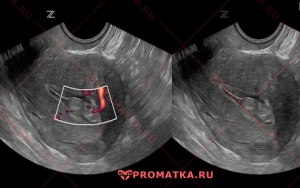

Полип эндометрия до 1 см может ли сам исчезнуть?

1. Полип эндометрия – это небольшая опухоль, образующаяся из слизистой оболочки матки.

2. Большинство полипов эндометрия могут быть диаметром до 1 см и чаще всего обычно не вызывают симптомов.

3. Однако, в некоторых случаях полип может стать причиной кровотечения из матки, болей внизу живота или бесплодия.

4. Несмотря на то, что полипы редко бывают злокачественными, их обычно рекомендуется удалить, особенно если они вызывают симптомы.

5. Полипы эндометрия обычно не исчезают сами по себе. В большинстве случаев они требуют удаления с целью предотвращения возможных осложнений.

6. Удаление полипов обычно производится с помощью гистероскопии – минимально инвазивной процедуры, при которой полип удаляется с помощью специального инструмента, вводимого через шейку матки.

7. После удаления полипа рекомендуется следить за состоянием эндометрия и проводить регулярные обследования, чтобы исключить возможное повторное образование полипов.

В заключение, не стоит полагаться на то, что полипы эндометрия могут исчезнуть сами по себе. Важно обратиться к врачу для оценки состояния и принятия необходимых мер по удалению полипов, если это необходимо.